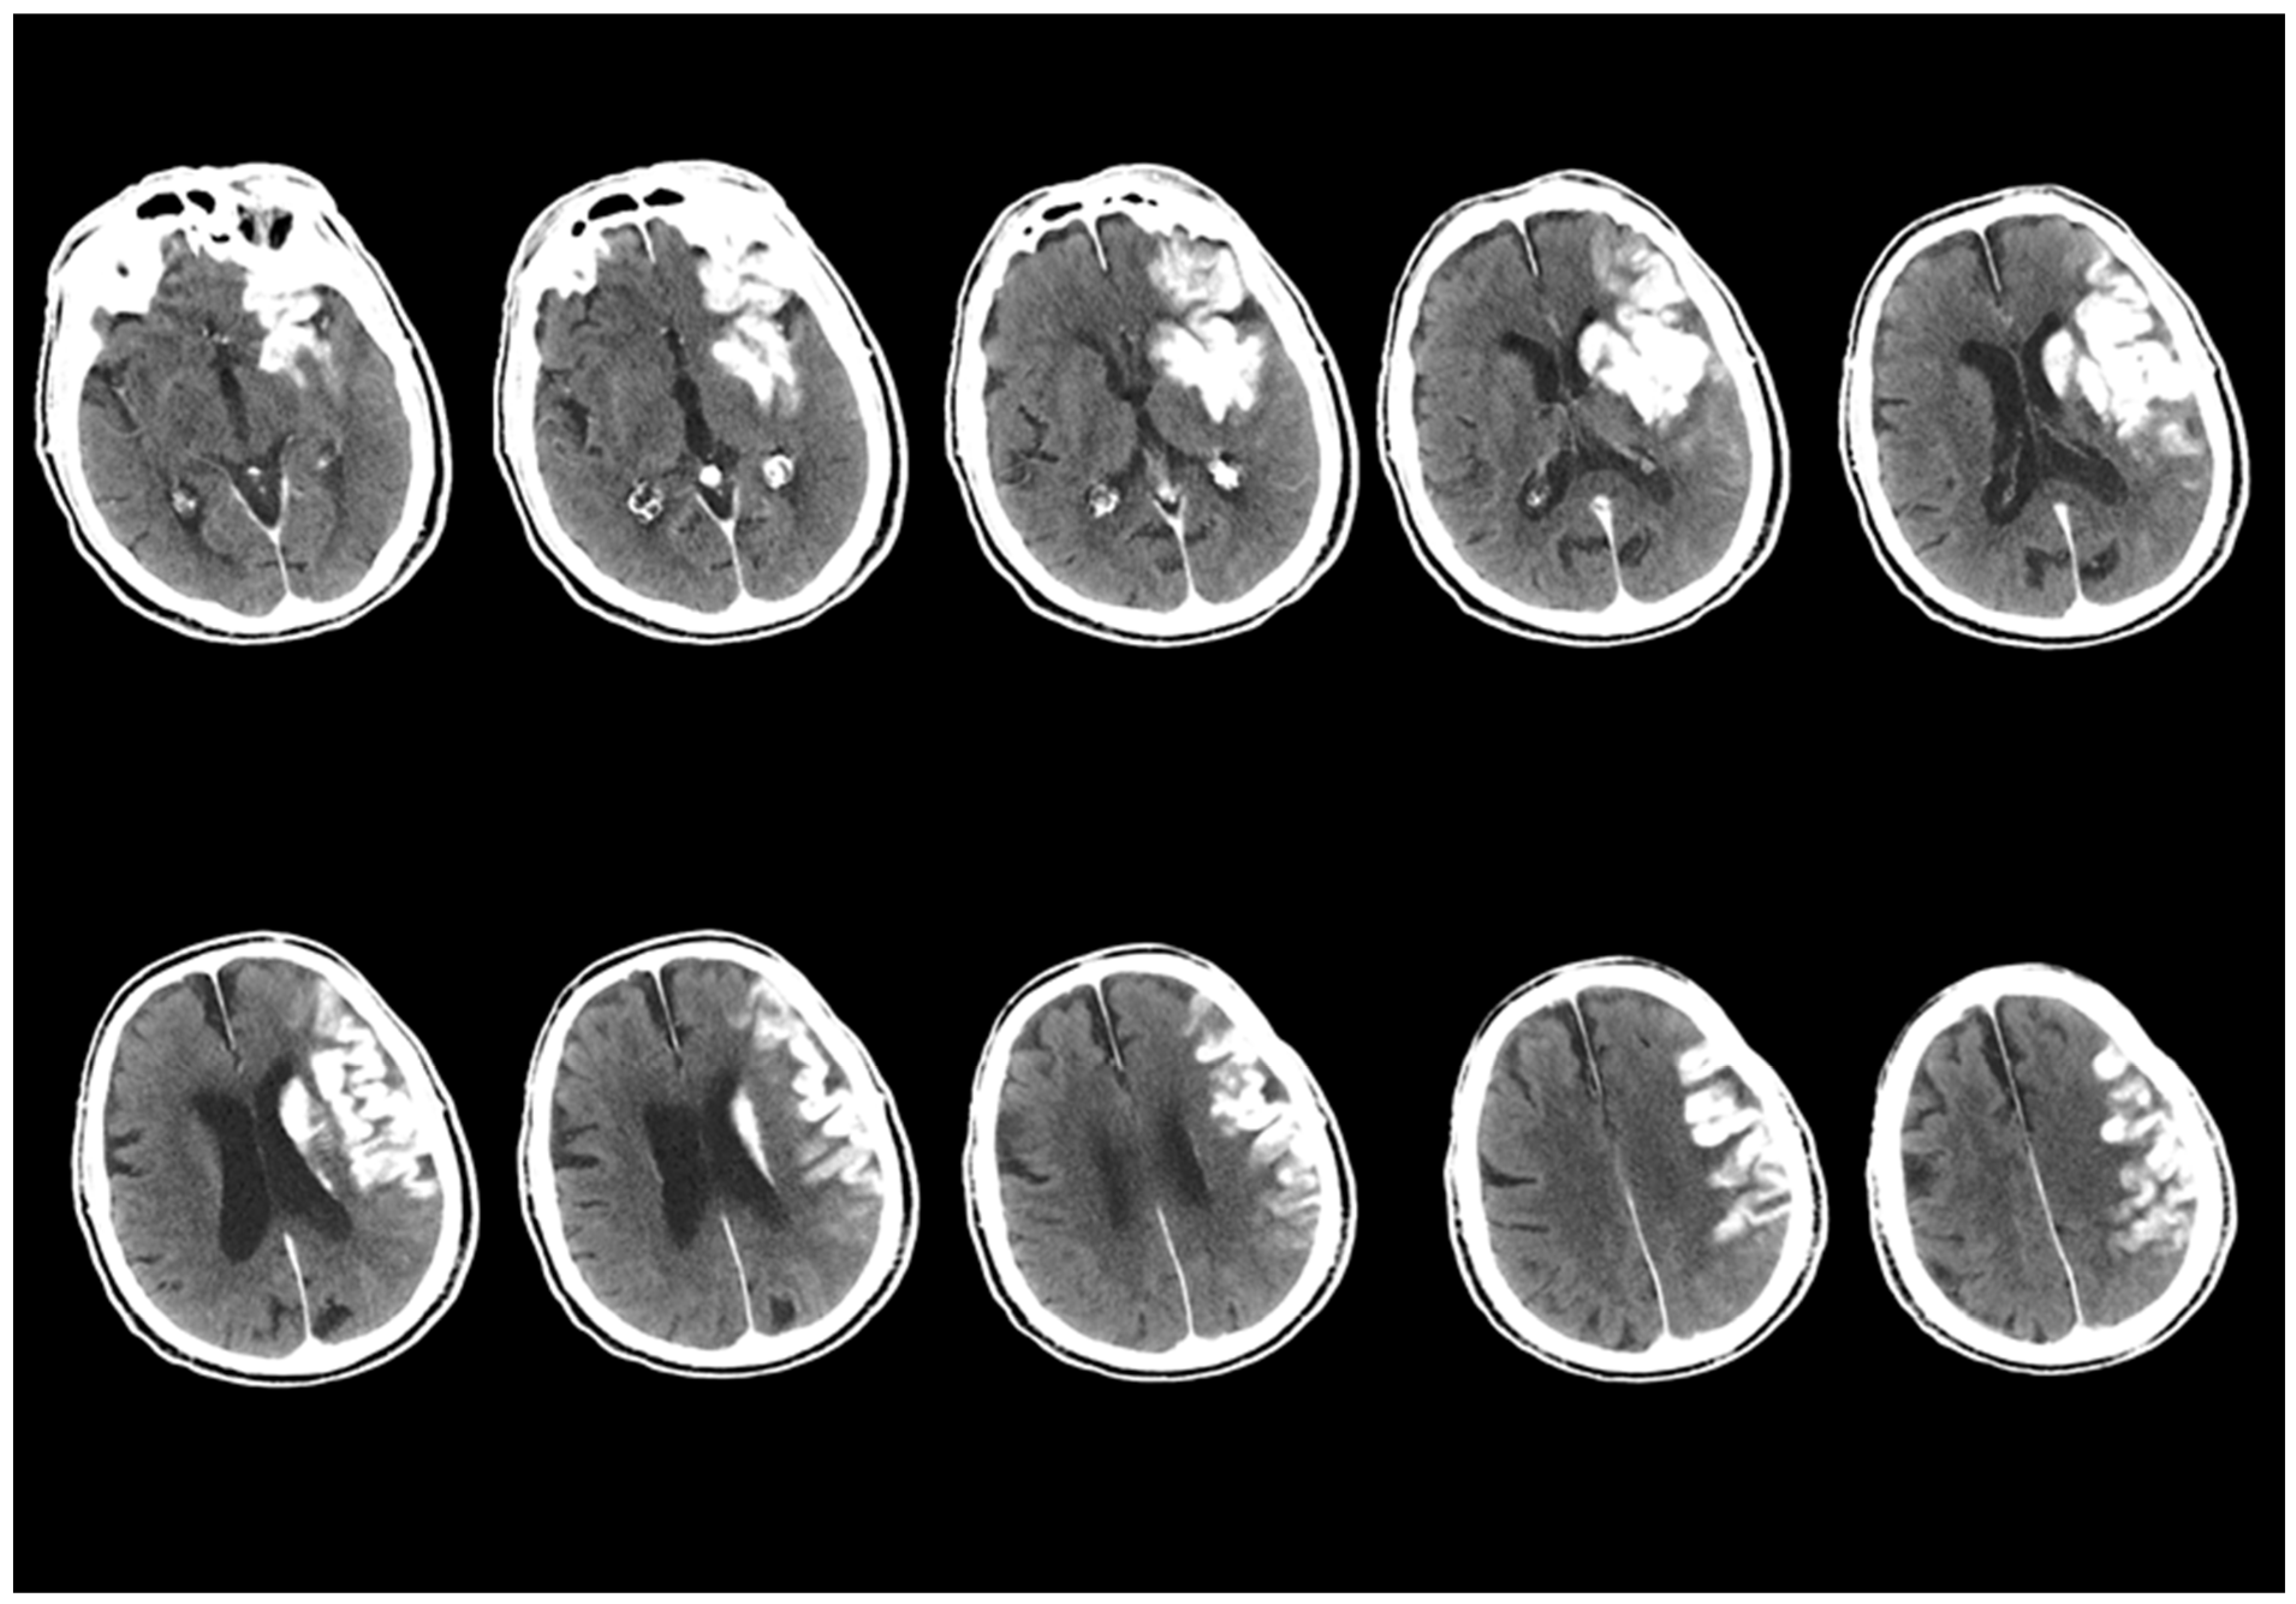

- Contrast Accumulation: The first scan found in the NCCT and the follow-up scan in the NCCT met all of the following conditions;

- Sequential follow-up scan showed hyperdensity that completely disappeared without leaving a hematoma area.

- Sequential follow-up scans show no newly developed hyperdense area.

- In sequential follow-up scans, hyperdensity that gradually decreases and completely disappears in NCCT images after 72 h.

- Hemorrhagic Transformation: The initial scan shows NCCT, and the follow-up scan shows NCCT meeting any of the following conditions.

- Hyperdensity that does not decrease or remains constant.

- Increase in hyperdensity size.